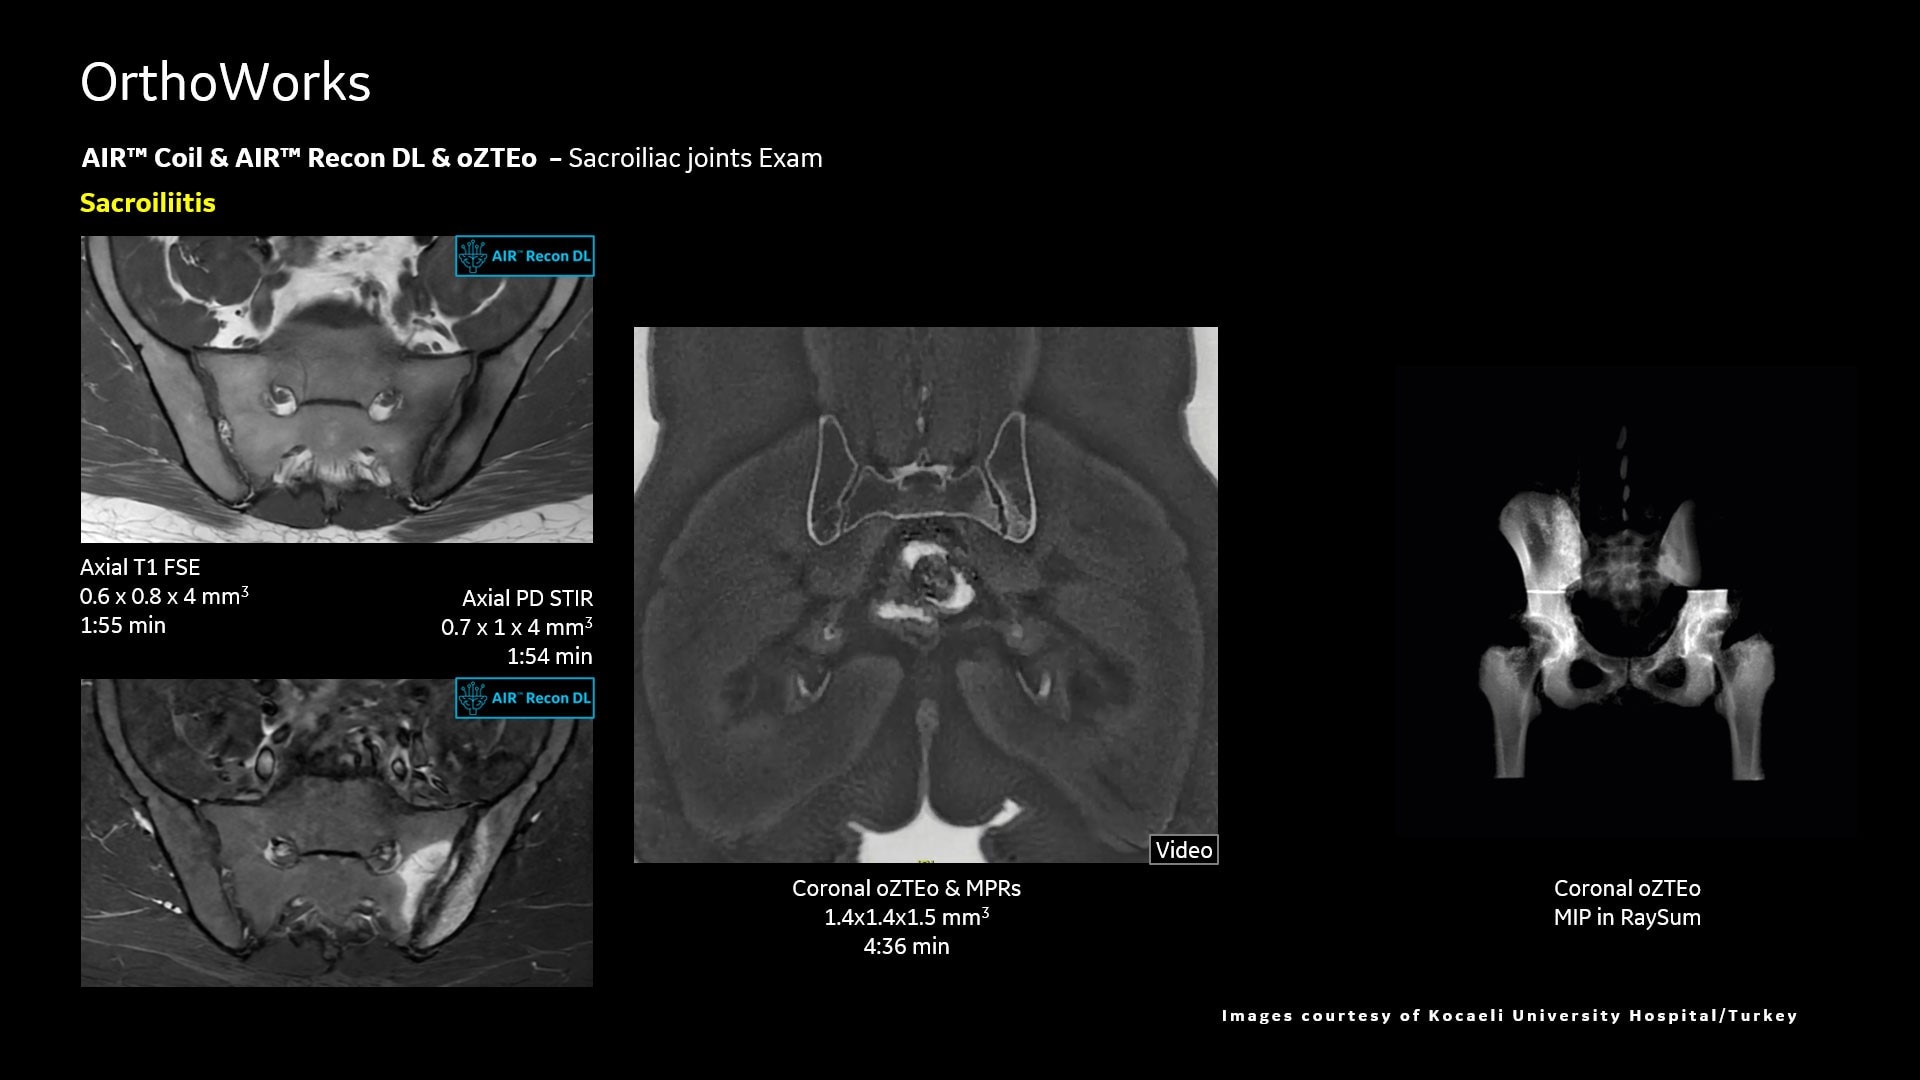

AIR™ Recon DL improves SNR and image sharpness, enabling shorter scan times

Up to 50% faster acquisition time with AIR™ Recon DL

Achieve a 25% efficiency gain with Ultra High Efficiency (UHE) gradient system. Fast, clear Total Digital Imaging (TDI) increases SNR by 25%. Improved IQ in 80% of cases without added time. Acquire higher SNR without a time penalty and get images virtually free of artifact with AIR™ Recon DL.***

Attain a 59% productivity gain in exam setup and 37% reduction in table time with AIR Touch™. Five times faster set-up time and four times fewer mouse clicks with AIR x™. Achieve up to a 50% faster acquisition time with AIR™ Recon DL.***